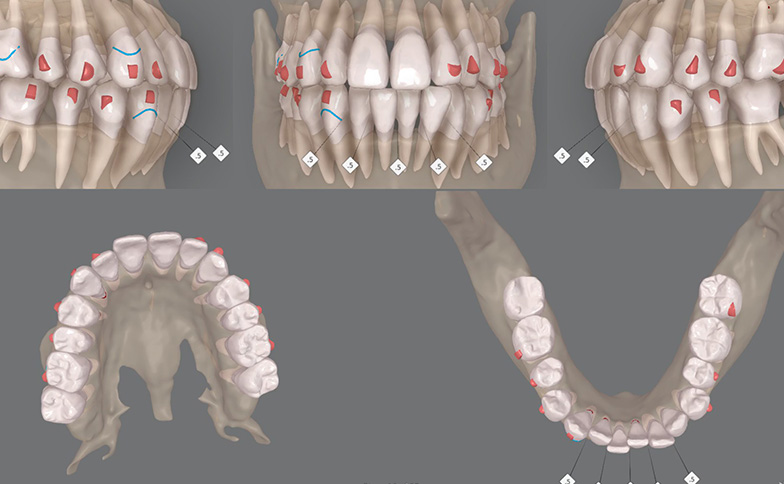

当院では、インビザラインのシミュレーションソフト(クリンチェック)とCTデータを連動させています。

「動かせる限界」を見極める

CTデータを重ね合わせることで、表面からは見えない「顎の骨の幅」を事前に把握できます。どこまでなら歯を安全に動かせるかを精密に算出できるため、無理な移動による歯根吸収(歯の根が短くなること)などのトラブルを未然に防ぎます。